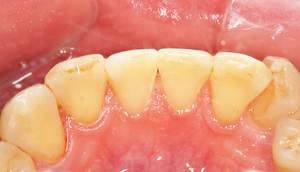

歯石除去

治療前

治療後

| 年齢 | 43歳・男性 |

| 主訴 | 歯石をとりたい |

| 治療内容 | 歯石除去 |

| 治療期間 | 30分 |

| 費用 | 約2,000円 |

| リスク・副作用 | ・歯ぐきの炎症が強いと歯石を取る際に出血することがあります ・処置後に歯がしみることがあります ・歯と歯の間に隙間ができるので、息が漏れ発音しにくいと感じることがあります ・歯ぐきの炎症が軽減すると歯ぐきが引き締まり、歯が長く見えることがあります |